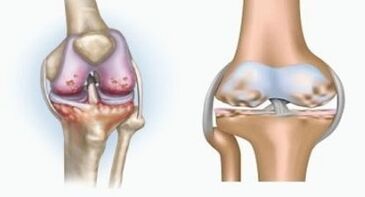

Her iki patoloji de eklemleri etkiler, ancak değişikliklerin doğasında farklılık gösterir.

Artrit ile

Artrit, bağ dokusunun iltihabıdır - birçok damar içeren ve lenf akışı sağlayan sinovyal bir membran. Enflamatuar süreç, eklem dokularının beslenmesinin ihlaline yol açar, bunun sonucunda eklem yağlama - sinovyal sıvı üretimi sınırlıdır.

Artroz ile

Artroz, eklemin kıkırdak dokusunun yok edilmesiyle ilişkili dejeneratif distrofik bir işlemdir. Kıkırdak yavaş yavaş yok edilir, kuru, eklemin kemikleri arasındaki mesafe azalır, bu da ağrının nedenidir. Şiddetli formlarda yıkım kemikleri etkiler. Daha gözenekli olurlar, yoğunluklarını kaybederler, kırılgan olurlar.

Örneğin, diz ekleminin artrit ve artrozu arasındaki fark nedir? Artrit ile eklem dokularının sinovyal kabuğu meydana gelir. Bu, eklemde sıcaklıkta bir artışa neden olur.

Eklem şişer, kalıcı bir ağrı sendromu gelişir ve hareket sırasında yoğunlaşır. Arthroz ile ağrı sadece fiziksel aktiviteden sonra meydana gelir, karakteristik bir krizi duyabilirsiniz veya eklemde tıklamalar, yavaş yavaş eklem deforme olur ve hareketliliği kaybeder.

Artrit ve parmakların artrozu ve ellerin elleri arasındaki fark, birinci hastalığın kürlenmesi ve ikincisinin olmamasıdır. Artrit ile sinovyal kabuk ve eklemin kapsülü dokunulur.

Kıkırdak ve kemik dokusunun yenilgisi sadece ihmal edilen bir durumda geç aşamalarda meydana gelir. Artroz ile, kıkırdak dokusu önce etkilenir ve daha sonra kemik, sinovyal membranın iltihabı ikincil kökenlidir, yani arka planlarına karşı gelişir.